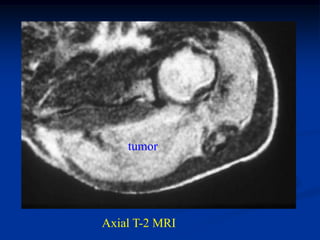

Case #253.2               Desmoid tumor

56 yr male with tender soft tissue mass volar aspect of wrist 6 mos